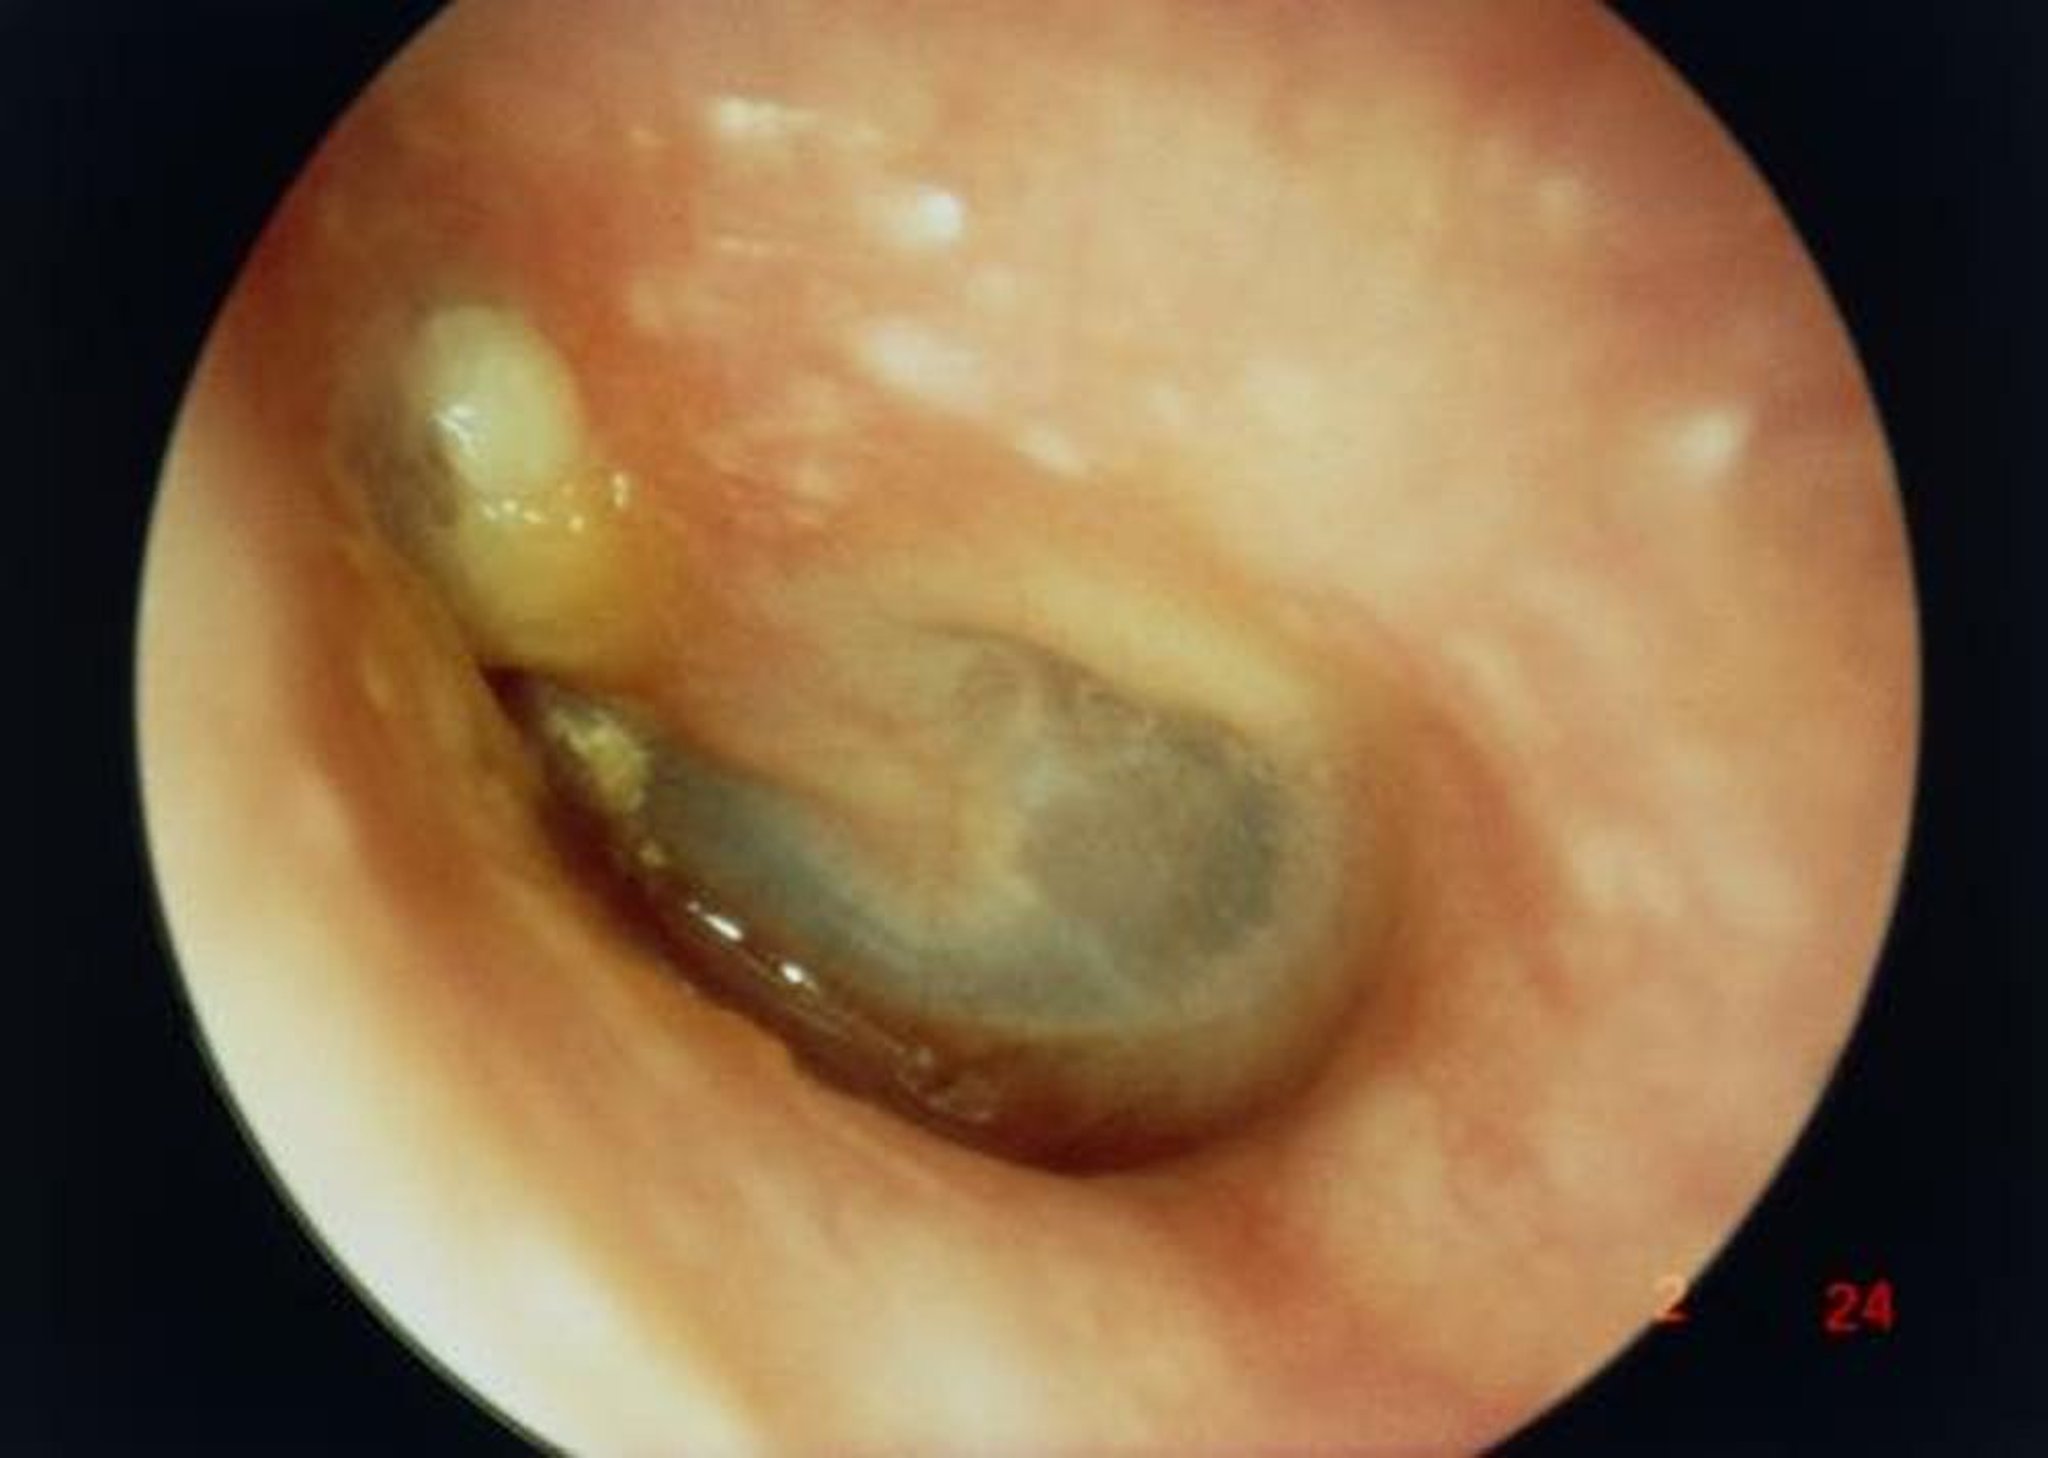

Холестеатома

In this image, the view along the external ear canal shows a large cholesteatoma (white mass on left superior to the short process of the malleus), resulting in a perforation of the tympanic membrane.